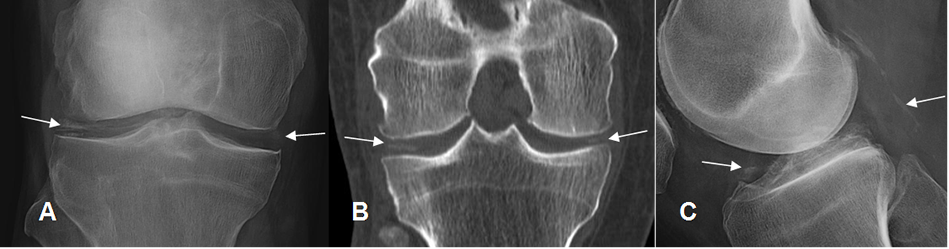

La enfermedad por depósito de cristales (Pirofosfatos de calcio) o condrocalcinosis, puede ocasionar calcificación de la sinovial, la cápsula articular, los ligamentos y tendones u ocasionar una artropatía atípica. (3).

El depósito de cristales en las articulaciones, ocasionan una respuesta inflamatoria de la sinovial y luego se unen a los condrocitos. (10). (Fig 35).

En la RM pueden detectarse algunas calcificaciones densas, como áreas hipointensas, utilizando secuencias en GE que tienen buena sensibilidad. En los meniscos algunos hallazgos en T1, deben diferenciarse de rupturas meniscales. (10).